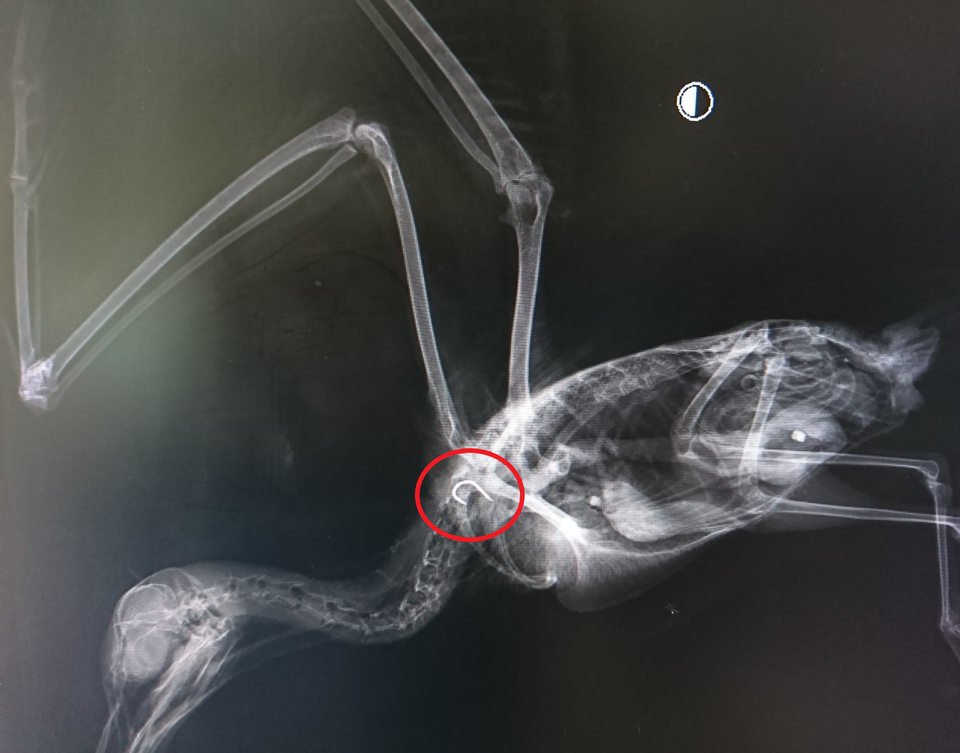

嘴の中はどうなっていたかというと...

外からだとわかりませんでしたが糸の塊が出来ていました。ちなみに釣り針本体は...

食道の中、鎖骨付近です。